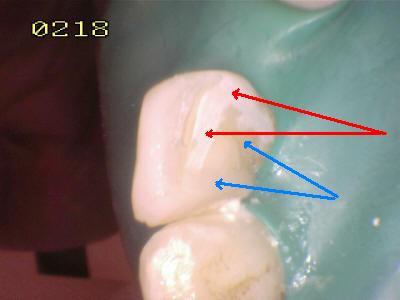

• Verificar el patrón de grabado del esmalte, suele tener el aspecto clínico de color tiza o falta de brillo (Flechas rojas: grabado del esmalte y La flecha azul: marca la resina compuesta de un material de obturación)